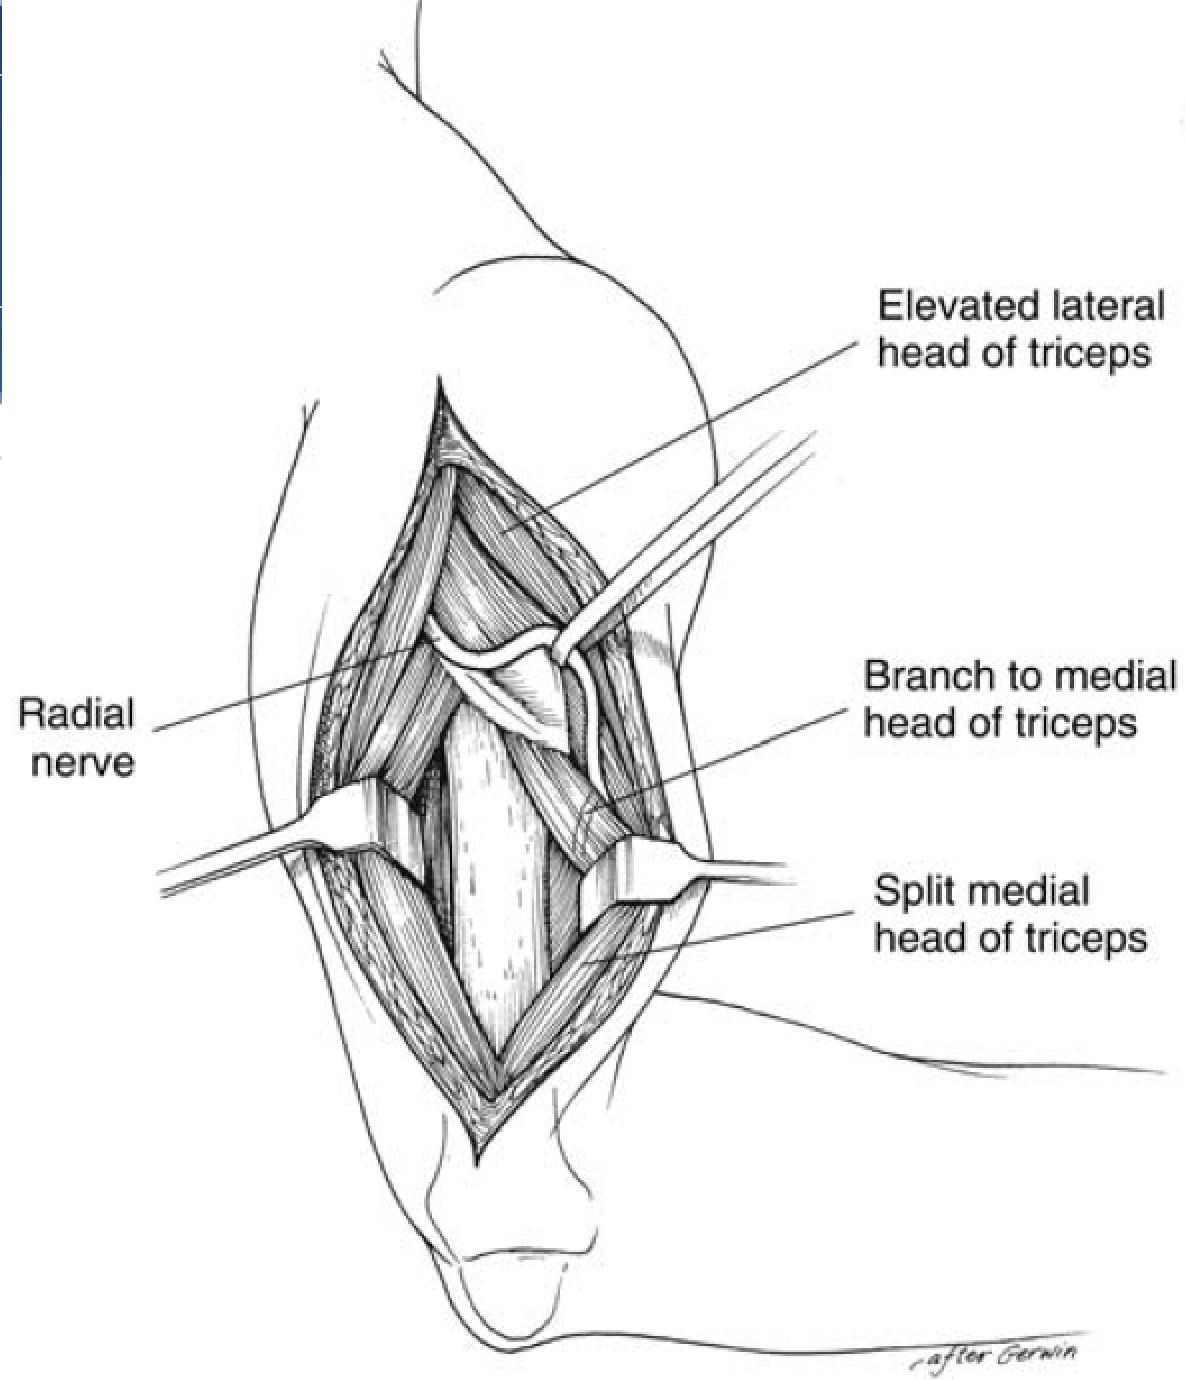

Triceps Splitting Approach

Interval: No internervous plane, split triceps (radial n.)

Approach: Start 8cm distal to tip of acromion (distal to axillary n.). Split between long and lateral heads superficially, and split medial head deep. Care taken to mark out spiral groove and dissect radial nerve.

Dangers: Axillary N. proximally, radial n. in spiral groove.

*thought that this approach can de-innervate medial head of triceps